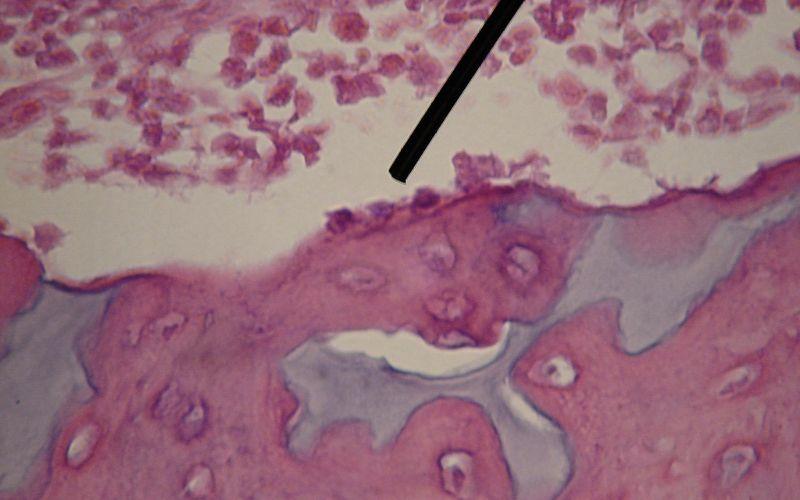

Osteoblastos bajo el microscopio. Fuente: Wbensmith, CC BY 3.0, Wikimedia Commons

Los osteoblastos son uno de los tres tipos celulares que están en el tejido conectivo especializado en el sostén estructural del cuerpo: el hueso. Estas células derivan de otras células llamadas células osteoprogenitoras y su función principal es la de la síntesis de la matriz ósea.

El hueso está compuesto por una matriz extracelular que se endurece gracias a la deposición de calcio, otorgando al tejido fuerza y rigidez, y por tres clases principales de células: los osteoblastos, los osteoclastos y los osteocitos.

Los osteoblastos se conocen como las células formadoras de hueso, mientras que los osteoclastos y los osteocitos son las células de reabsorción y de “laguna”, respectivamente. De estas, la clase más abundante corresponde a los osteocitos (más del 90%), seguido de los osteoblastos (5%) y en menor proporción los osteoclastos (1%).

• Según micrografías electrónicas, los osteoblastos presentan un abundante retículo endoplásmico rugoso y un complejo de Golgi altamente desarrollado, con numerosas vesículas secretoras, lo que da cuenta de la activa función de secreción de estas células.

• Se conocen como células “cuboidales” gracias a sus características morfológicas, y se encuentran formando capas unicelulares adheridas a las superficies óseas.